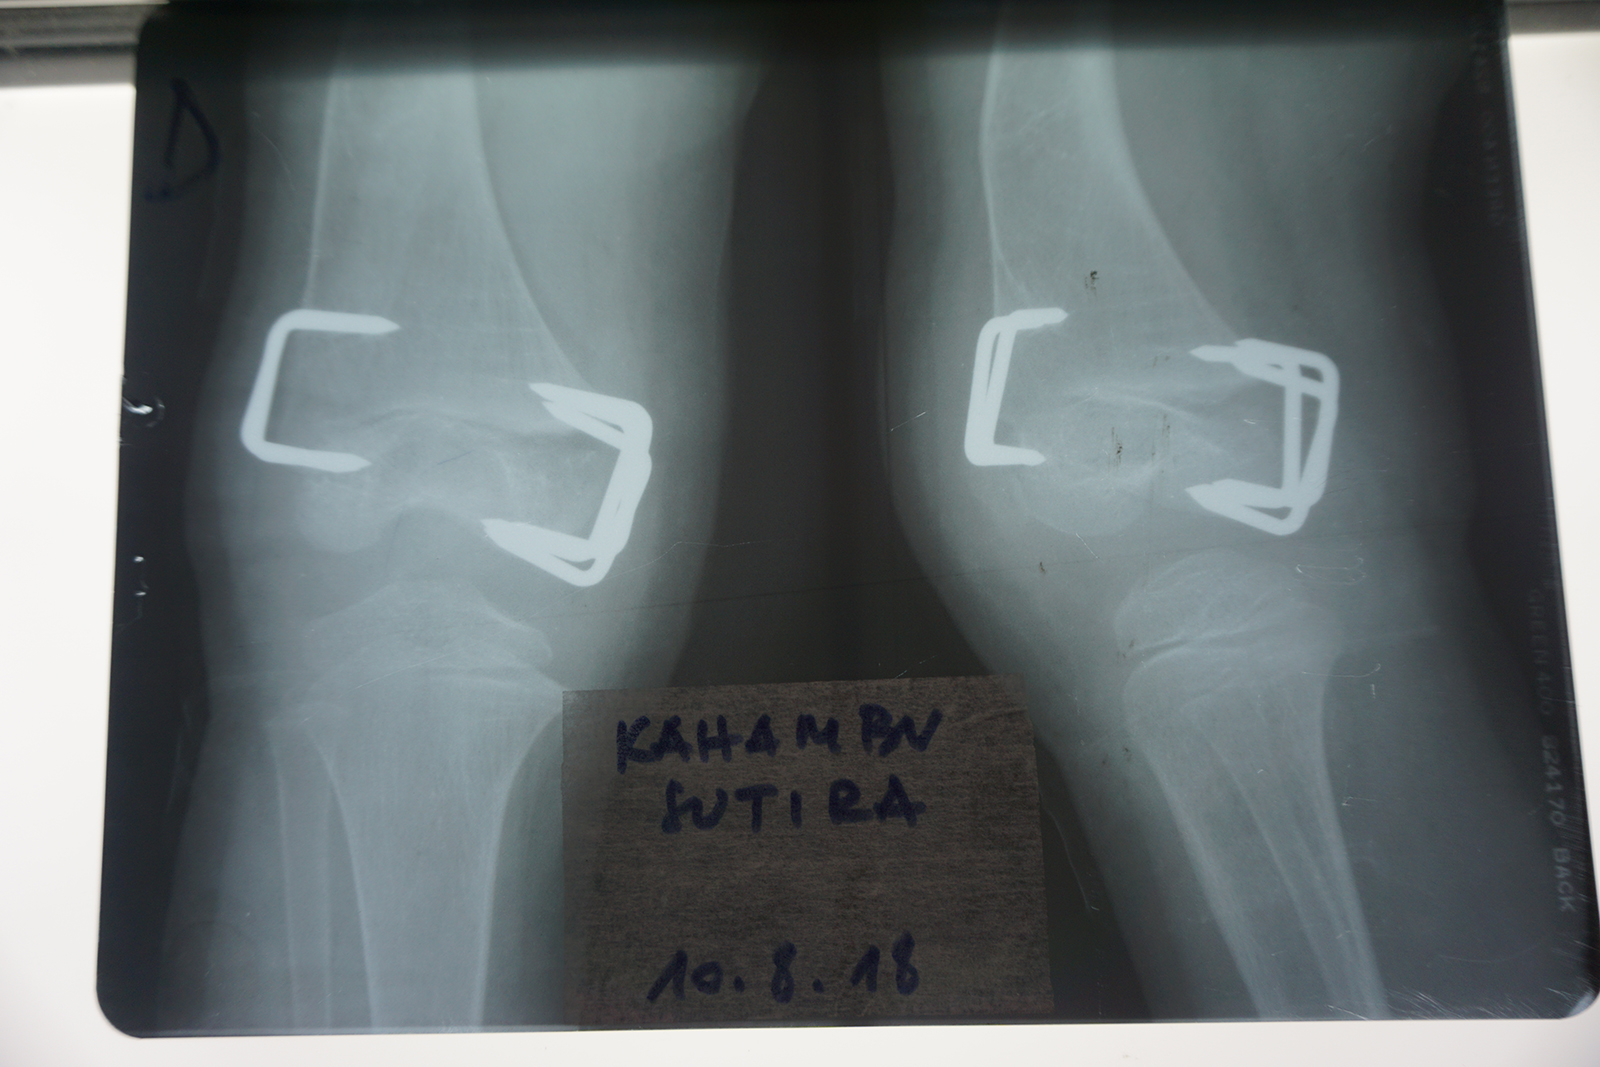

Wird das Wachstum auf einer Seite einer solchen Fuge gezielt gebremst, wächst der Knochen auf der gegenüberliegenden Seite weiter. Dadurch kann sich eine Achsfehlstellung über Monate oder Jahre allmählich selbst korrigieren. Die Wachstumshemmung erfolgt durch kleine Klammern oder Plättchen, die die Wachstumsfuge überbrücken und so deren Aktivität einschränken (Abb. 4).

Bei Arielle brachten wir im August 2017 Klammern an der Außenseite des rechten Kniegelenkes an, um die O-Bein-Stellung zu korrigieren (Abb. 5). Nach einigen Monaten war die Achsfehlstellung ausreichend ausgeglichen. Es blieb jedoch weiterhin die Überlänge des rechten Beines bestehen.

Um dieses Längenproblem zu behandeln, wurden im August 2018 zusätzlich Klammern an der Innenseite derselben Wachstumsfuge eingesetzt (Abb. 6). Dadurch wurde das Wachstum des rechten Beines insgesamt verlangsamt, ohne es vollständig zu stoppen. Andere Wachstumsfugen blieben weiterhin aktiv, jedoch wuchs das behandelte Bein nun langsamer als das unbehandelte linke. Auf diese Weise erhielt das linke Bein die Möglichkeit, im Wachstum aufzuholen.

Klammern an der Außenseite des rechten Kniegelenkes, November 2017

Korrektur O-Bein-Stellung, November 2017

August 2018